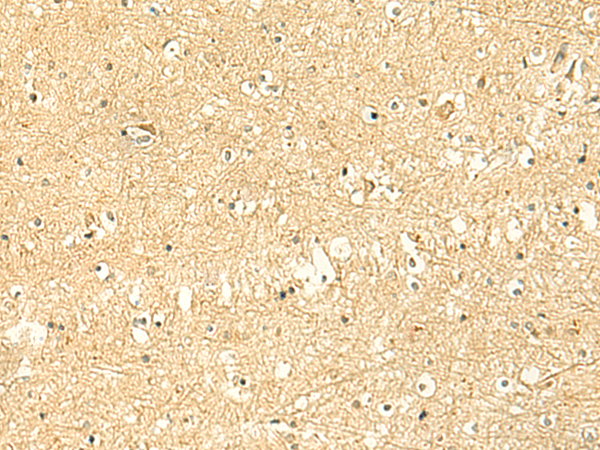

IHC positive control: |

Human esophagus cancer and Human brain |

IHC Recommend dilution: |

50-300 |